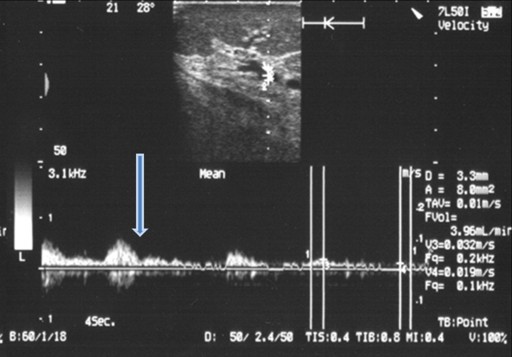

In Group 2 (3 cases, 13%), the splenic hilar arterial blood flow disappeared after the clamping of the splenic artery (Table 3), and it was unaffected by the subsequent clamping of the short gastric and left-gastroepiploic arteries, irrespective of the order in which they were clamped (Figure 5).

Figure 5. Intraoperative color Doppler ultrasound of the splenic hilum at distal pancreatectomy in cases of an interrupted gastroepiploic arcade. The arterial blood flow disappeared after splenic artery cross-clamping. It was unaffected by the subsequent clamping of the left-gastroepiploic artery and the short gastric arteries irrespective of the order in which they were clamped. |